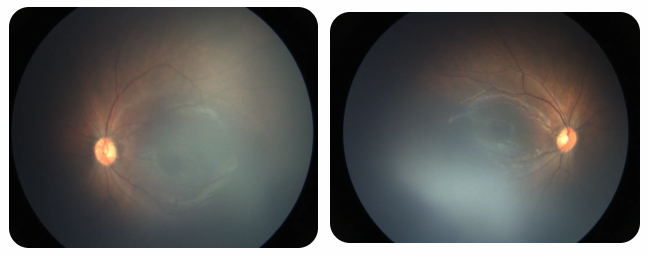

廈門眼科中心黎曉新名醫(yī)工作室曾接診一名31周出生的早產(chǎn)兒,出生體重僅1300克。由于家長缺乏篩查意識(shí),直到孩子5個(gè)月大時(shí)眼睛仍不會(huì)追光,才前來就診。檢查發(fā)現(xiàn),患兒ROP已進(jìn)展至4B期,因纖維血管增殖牽拉導(dǎo)致視網(wǎng)膜脫離,錯(cuò)過了最佳治療窗口。盡管黎曉新教授團(tuán)隊(duì)成功實(shí)施了玻璃體切割手術(shù),孩子的視力仍存在不可逆損傷。此后,孩子開啟了長期隨診復(fù)查、治療的“護(hù)眼征程”,目前其右眼矯正視力為0.6,左眼為0.8。

近期術(shù)前檢查:

早產(chǎn)兒視網(wǎng)膜病變

術(shù)后復(fù)查:

相比之下,另一位早產(chǎn)寶寶在出生5周后,生命體征穩(wěn)定之時(shí),便在產(chǎn)科醫(yī)生的建議下轉(zhuǎn)診至廈門眼科中心。經(jīng)篩查確診為Ⅲ期ROP,黎曉新教授團(tuán)隊(duì)及時(shí)為其進(jìn)行了激光治療。半年后復(fù)查顯示,寶寶的視網(wǎng)膜血管發(fā)育正常,視力發(fā)育與足月兒童無異。